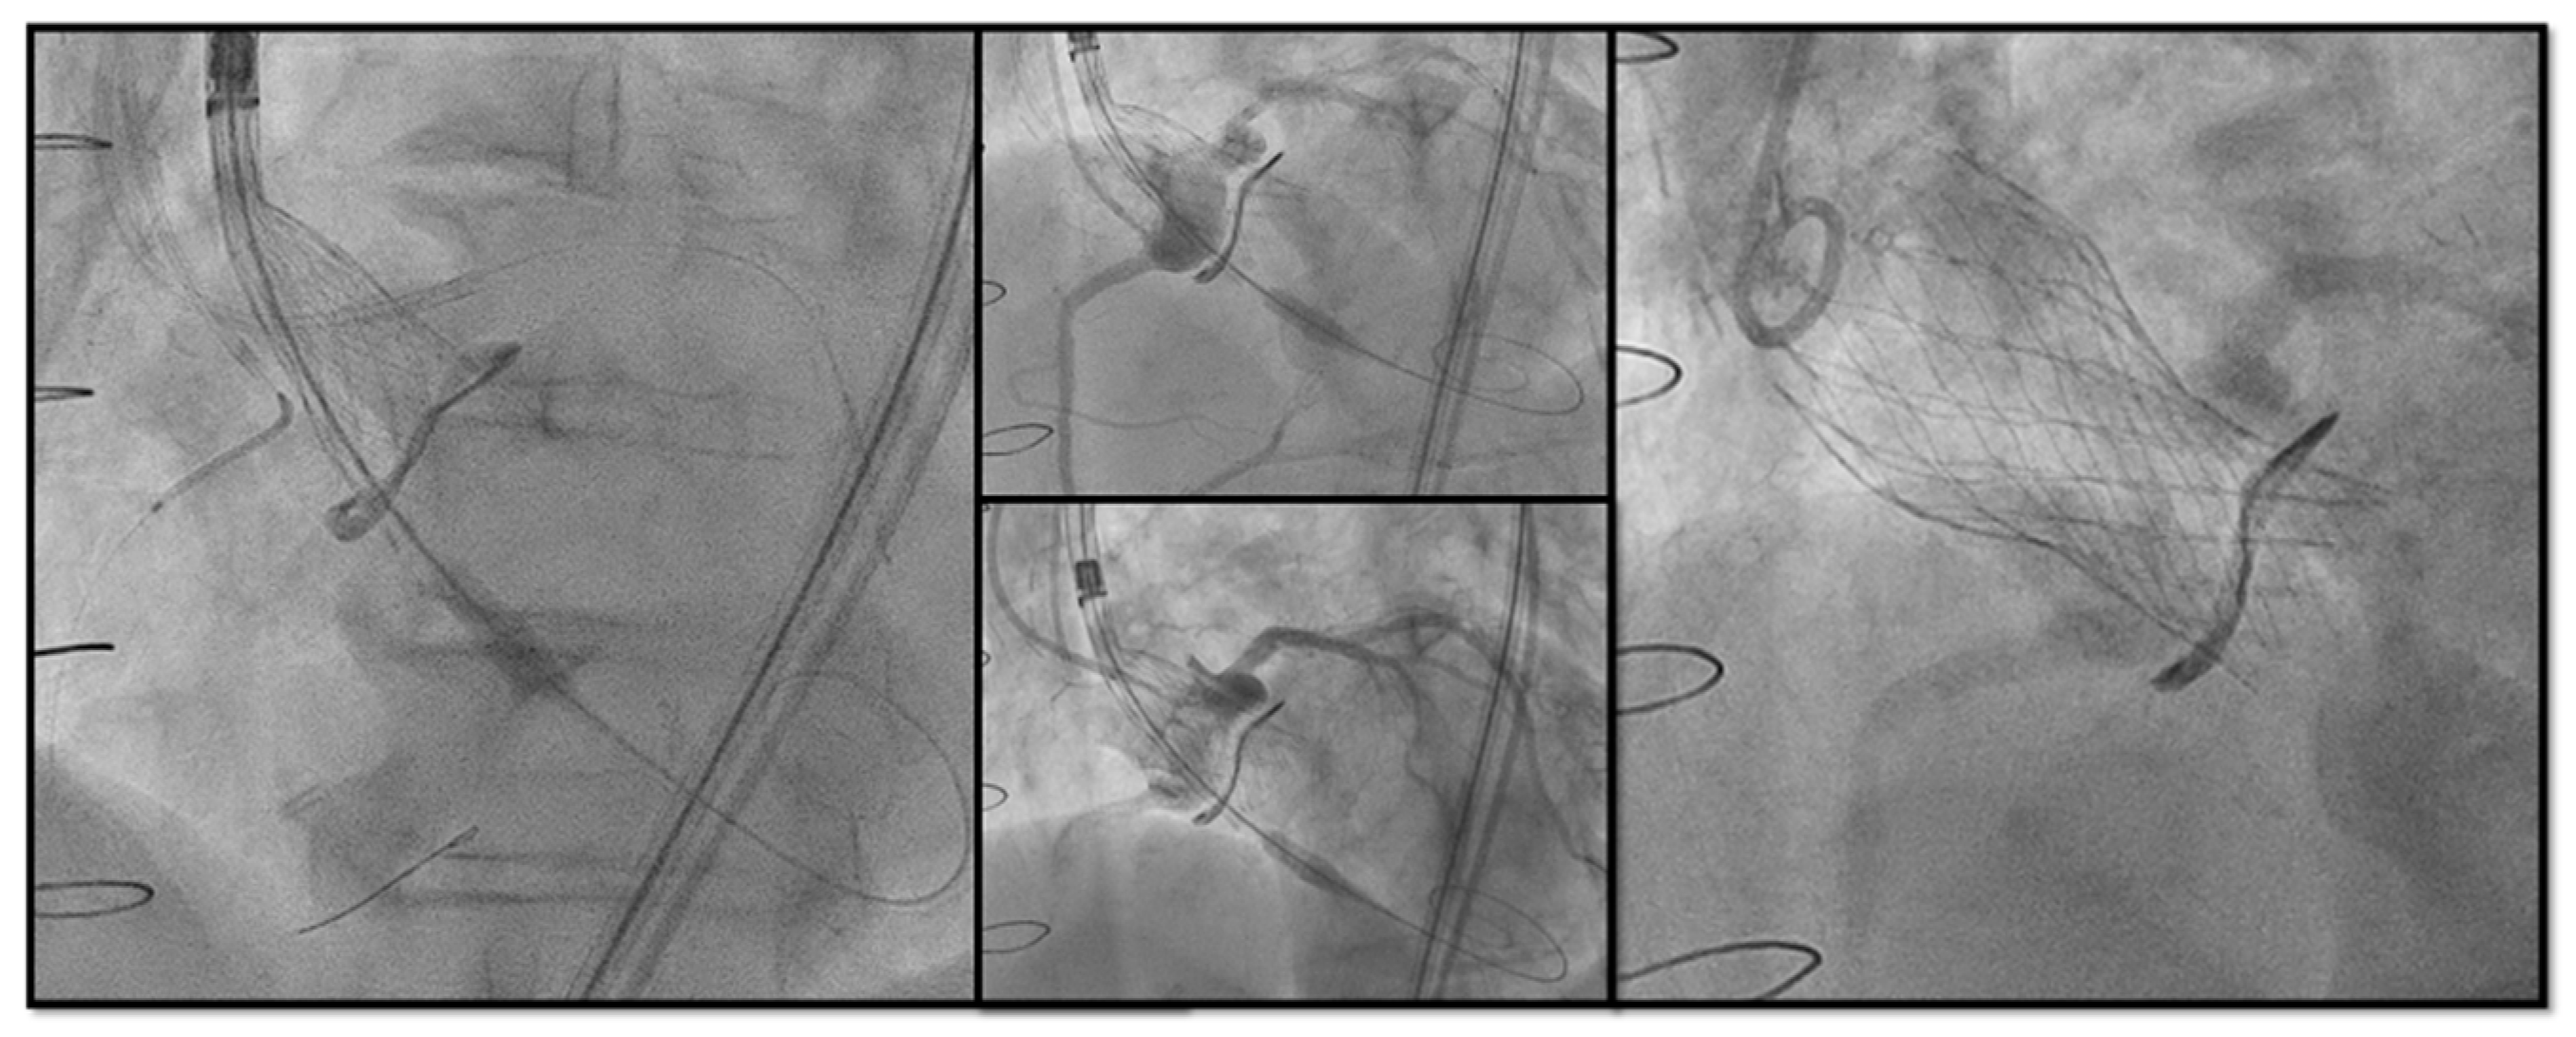

- Chimney snorkel stenting technique: Wiring the coronary artery and putting a stent on standby to be eventually implanted after THV deployment if the coronary flow is inadequate at angiographic control (Figure 7);

Figure 7. Double Chimney Stenting Technique with 4.0 × 33 Everolimus eluting stent implantation at ostial RCA and 4.0 × 18 at proximal left main before Corevalve Evolut Pro + 23 mm valve-in-valve implantation in a Mitroflow 23. - -